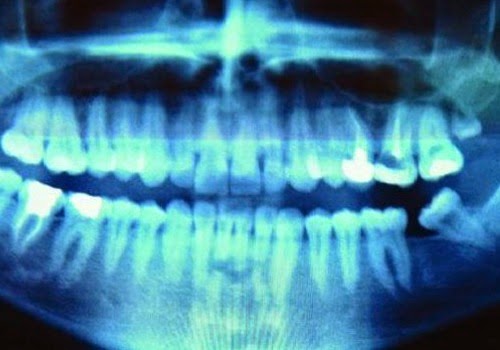

CANCRO PROVOCATO DAL TRATTAMENTO AI DENTI?

È possibile che un intervento medico dentistico sia la causa di diverse malattie cardiovascolari e tumori? Per il dottor Bill Henderson, ricercatore e membro del consiglio di amministrazione della Fondazione indipendente sulla ricerca del cancro, il 90% dei malati di cancro avrebbe avuto il trattamento al canale radicolare.

Questo tipo di intervento può causare l’estrazione di un dente o il riempimento della camera di un dente devitalizzato. Nel secondo caso il dente “morto” è riempito con la cosiddetta guttaperca in modo che il sangue non possa più circolare all’interno dei tubuli che compongono il dente. Secondo Henderson così facendo si produrrebbero batteri capaci di produrre tossine in totale tranquillità, visto che a causa del riempimento sono isolati dall’esterno.

A questo punto i batteri orali potrebbero trasformarsi in organismi aggressivi ed estendersi per tutta la bocca e non solo.

Bill Henderson si rifà alla teoria vecchia di oltre un secolo di due dentisti, Weston Price e Douglas Cook. Secondo quest’ultimi ogni malattia degenerativa cronica è connessa al trattamento del canale radicolare: disturbi cardiaci, artirti, tumori, patologie neurologiche e così via fino al cancro.

Henderson sull’argomento ha scritto il libro Cancer Free ma è giusto anche dire che questo libro è stato criticato da altri specialisti che non concordano con un simile collegamento e negano le tesi affermate nel testo.